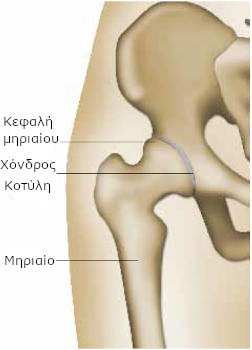

Το μηριαίο είναι το οστό που βρίσκεται στο εσωτερικό του μηρού. Στην άρθρωση του ισχίου, το ανώτερο μέρος του μηριαίου οστού (κεφαλή μηριαίου), θηλυκώνει σε μια κοιλότητα της λεκάνης, που ονομάζεται κοτύλη.

Οι δυο επιφάνειες της άρθρωσης, που εφάπτονται, καλύπτονται από ένα σχετικά μαλακό ιστό, που ονομάζεται χόνδρος και τους επιτρέπει να γλιστρούν μεταξύ τους εύκολα και ανώδυνα.

Η άρθρωση σταθεροποιείται από ένα σάκο (αρθρικός θύλακος) και περιβάλλεται από ένα υγρό (αρθρικό υγρό), που χρησιμεύει ως λιπαντικό, διευκολύνοντας την κίνηση, όπως το λάδι τα γρανάζια μιας μηχανής.